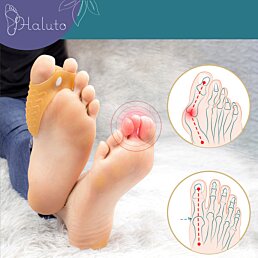

Hallux valgus (vybočený palec na nohe)

Prejavy a príčiny

Hallux valgus je odborné pomenovanie stavu, pri ktorom sa palec na nohe vychyľuje zo svojej osi smerom k ostatným prstom. Takto ohnutý kĺb sa stáva bolestivým a postupne dochádza k deformácii celej prednej časti chodidla. K faktorom, ktoré prispievajú k vzniku tohto ochorenia, patrí nevhodná obuv, preťažovanie chodidiel, ploché nohy a v neposlednom rade tiež genetika.

Riešenie

Hallux valgus sa, bohužiaľ, neinvazívnym spôsobom vyliečiť nedá. Vhodnými produktmi sa však dá spomaliť jeho vývoj a tiež zlepšiť každodenný komfort. Pomôže vám korektor na halluxy, ktorý udrží palec v správnej polohe. Prekrývajúce prsty môžu spôsobovať bolestivé otlaky na nohách - aby ste im predišli, nezabudnite na gélové chrániče prstov. Dbajte na výber vhodnej obuvi, prípadne ju doplňte o ortopedické vložky.